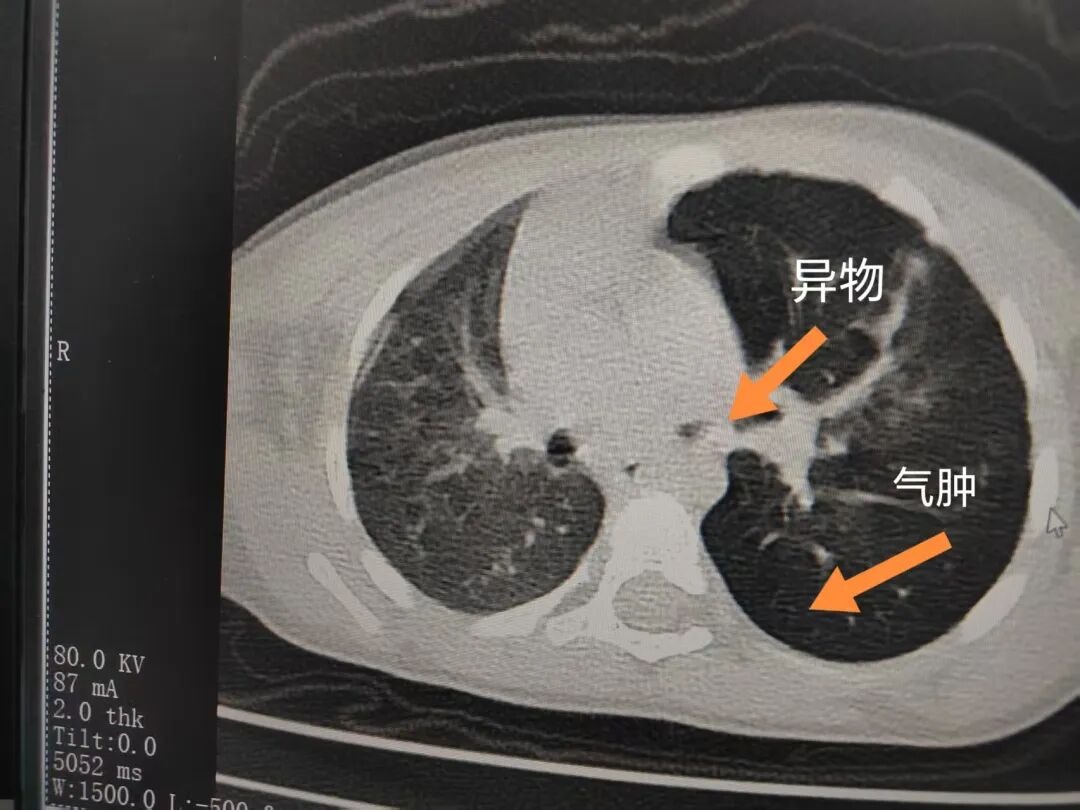

三天后(11月13日),趙寶出現(xiàn)高熱、咳喘加重,家長著急了,再次帶他來到醫(yī)院。CT檢查顯示左肺過度充氣,左肺上下葉支氣管主干見不規(guī)則高密度影,左肺上葉可見大片狀密度增高影,縱隔窗實變,提示為“左側(cè)支氣管內(nèi)異物并繼發(fā)性改變,左肺上葉舌段肺膨脹不全”。

市二院小兒呼吸內(nèi)科副主任楊亞娟介紹,異物誤入氣道可能導(dǎo)致氣道阻塞,嚴(yán)重時可引發(fā)窒息,甚至危及生命。若異物進入支氣管,造成不完全堵塞,可引起阻塞性肺氣腫;如完全堵塞支氣管,則可能導(dǎo)致肺組織萎縮,形成肺不張。此外,若異物存留時間較長,或為植物性異物,容易合并細(xì)菌感染,產(chǎn)生膿性分泌物,進而發(fā)展為肺炎。她強調(diào),盡早診斷并取出異物,是減少并發(fā)癥、降低病死率的關(guān)鍵。